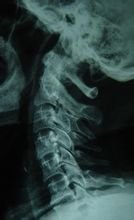

臨床表現

缺血性肌攣縮早期主要臨床表現為"5P",即Pain(疼痛),Paresthsia(感覺異常),Paralysis(麻痹),Pulseless(無脈),Pale(蒼白)。晚期形成典型的爪狀畸形。